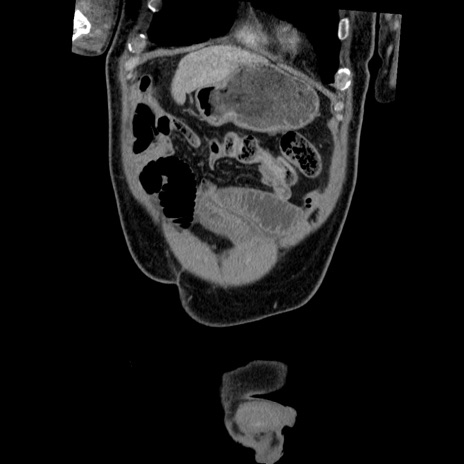

症例22(冠状断像)

【症例】50歳代男性

【主訴】腹痛

【現病歴】AVMからの被殻出血のため回復期リハ病棟入院中。 本日午後3時頃急に下腹部痛が出現した。

【既往歴】AVM、被殻出血、虫垂炎、高血圧

【身体所見】意識晴明、左半身不全麻痺、会話の理解は良好、36.5°C、腹部:膨隆、全体に板状硬、下腹部正中に圧痛点あり、反跳痛-、筋性防御不明、右下腹部にope scar

【データ】WBC 9400、CRP 0.06